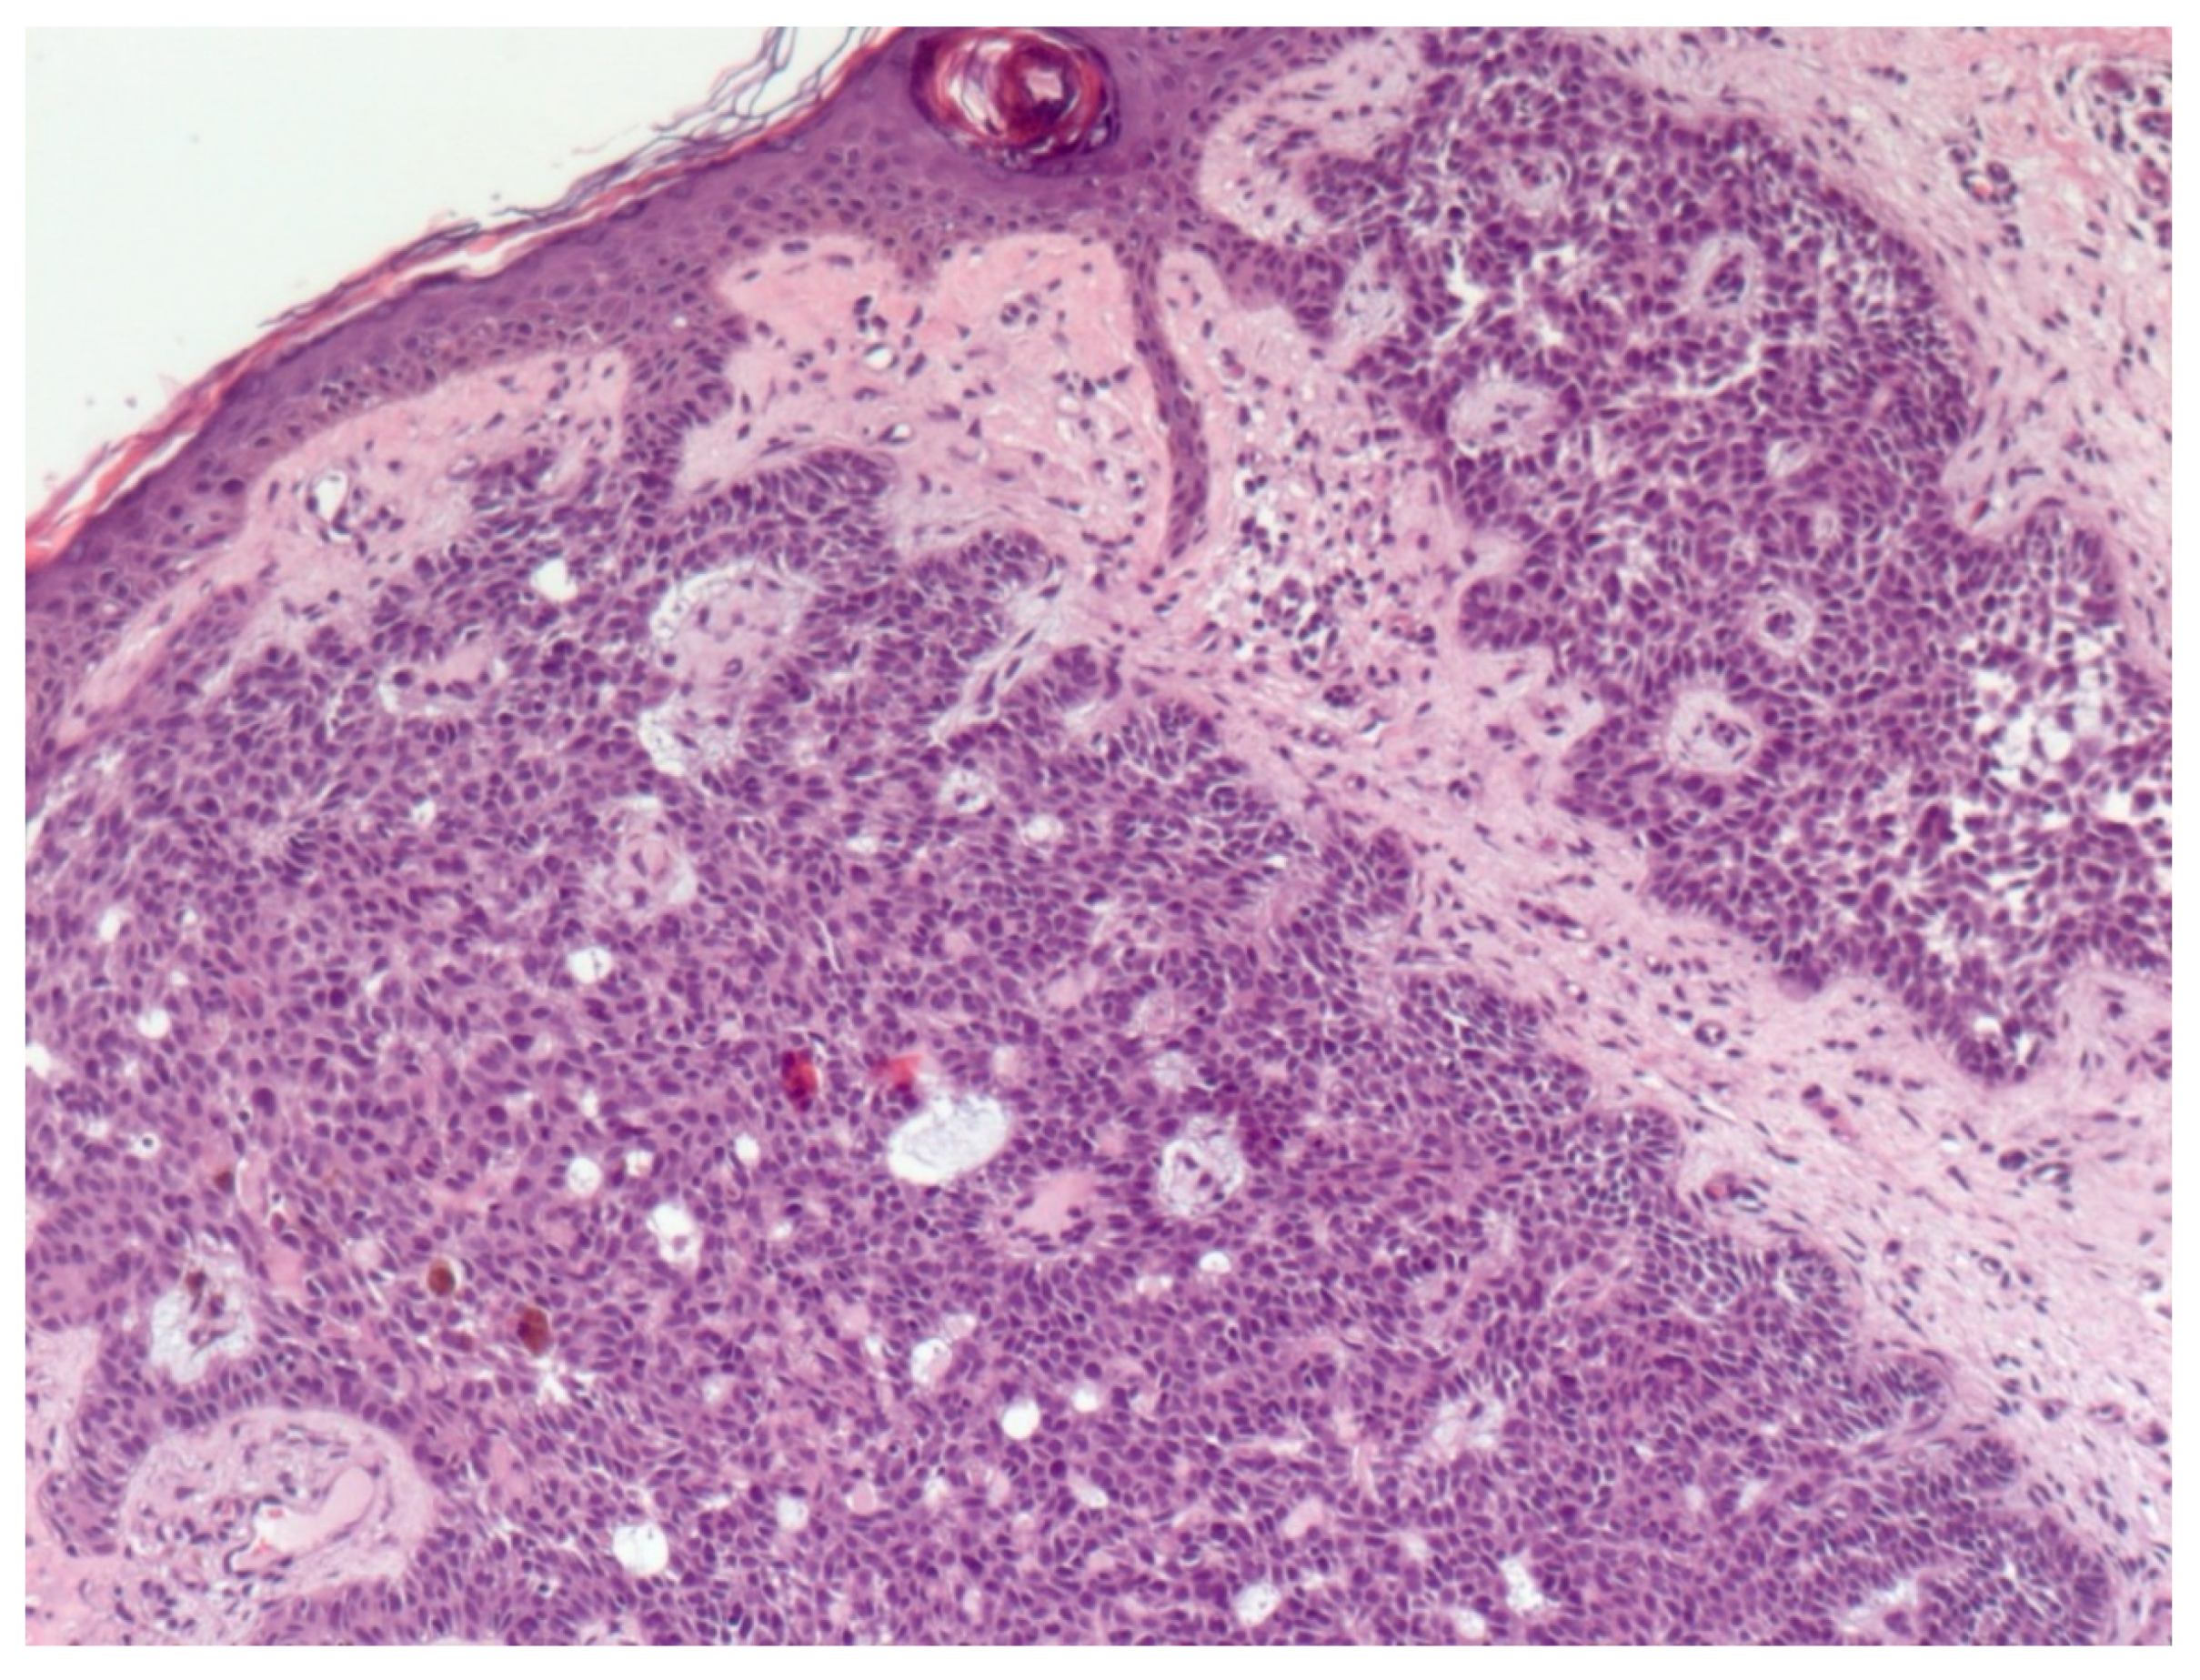

4. Histopathological Features of BCC

- Paolino, G.; Donati, M.; Didona, D.; Mercuri, S.R.; Cantisani, C. Histology of Non-Melanoma Skin Cancers: An Update. Biomedicines 2017, 5, 71. [Google Scholar] [CrossRef] [Green Version]